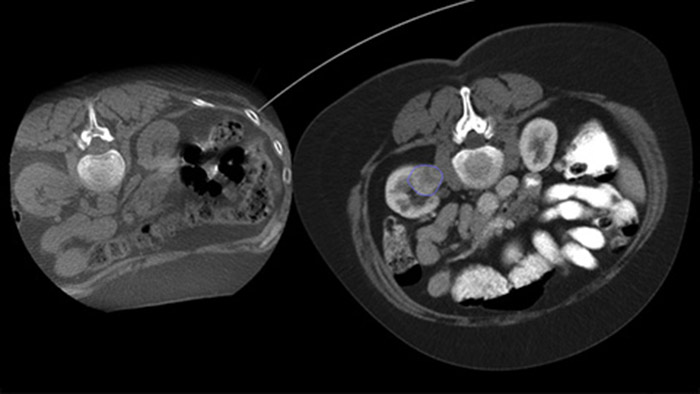

Dual View allows the overlay of a pre-procedure 3D image (CT/MR/PET-CT) on an intra-procedure 3D CBCT Dual to better visualisation the lesions and access critical input for needle planning.

With CBCT acquire a post-ablation CBCT to demonstrate the extent of tumor coverage and confirm completeness of your treatment.